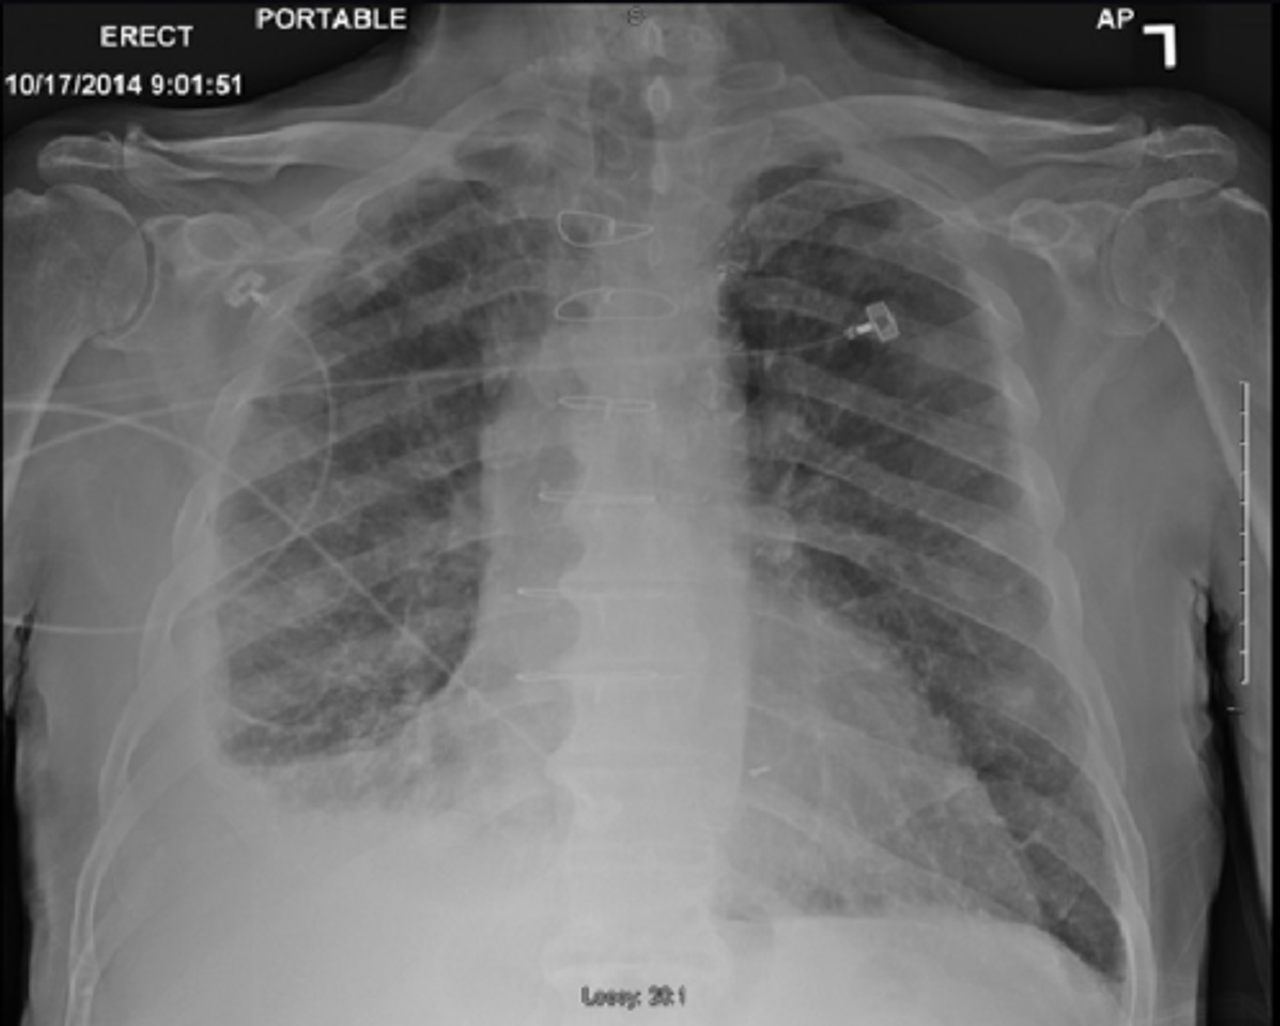

Silicosis is a fibrosing or stiffening of lung tissue that results from an inflammatory or immune response to combat the inhaled silica dust. Other diseases are also known to occur, including lung cancer and autoimmune diseases that mainly develop as a condition known as scleroderma.